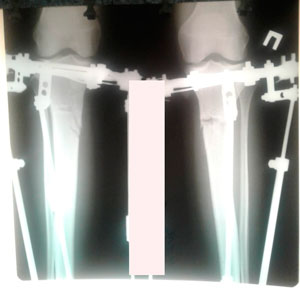

Исходник - 24 года.

Диагноз: варусная деформация голеней. Ротация с обеих сторон.

Дата операции - 16.10.2019г.

на фиксации

Вложения